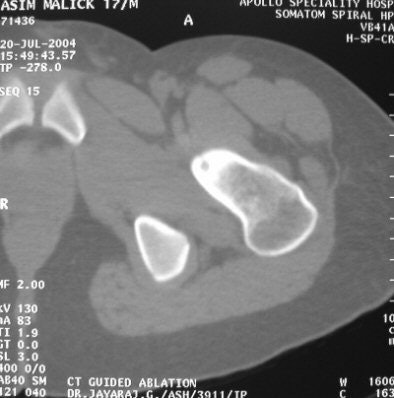

| Seventeen-year old patient with tumour in the neck of the femur. All images courtesy Dr Jayaraj Govindaraj, Apollo Speciality Hospital. |

In the procedure Govindaraj performed, CT was used to localise the lesion, and axial slices of 2-mm thickness were obtained. Percutaneous RF ablation was performed under CT guidance, the RF probe was introduced into the nidus, and the tumour tissues were heated to a temperature of 100 degrees centigrade for three to five minutes.